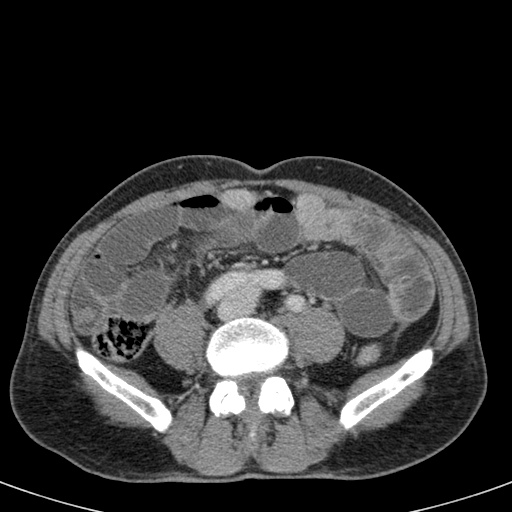

Nếu quai kín dài hơn và định hướng vuông góc với mặt phẳng cắt, chúng ta sẽ thấy một cụm quai ruột như trong ca lâm sàng bên trái.

Đôi khi điều này khó nhận biết chỉ trên các lát cắt ngang và các tái tạo mặt phẳng coronal hoặc sagittal có thể hữu ích.

Trong ca này, cũng có phù nề mạc treo và cổ

Bên trái là các hình ảnh CT bổ sung của cùng bệnh nhân nêu trên.

Hãy quan sát các hình ảnh này, tìm kiếm các dấu hiệu chính rồi tiếp tục.

Đầu tiên, chúng ta thấy đại tràng xuống xẹp và đại tràng lên không giãn, do đó đây không thể là xoắn đại tràng sigma.

Thứ hai, chúng ta thấy một cấu trúc hình mỏ chim ở góc phần tư dưới bên phải, đây là vị trí xoắn của ruột.

Ở góc phần tư dưới bên trái, chúng ta thấy manh tràng giãn.